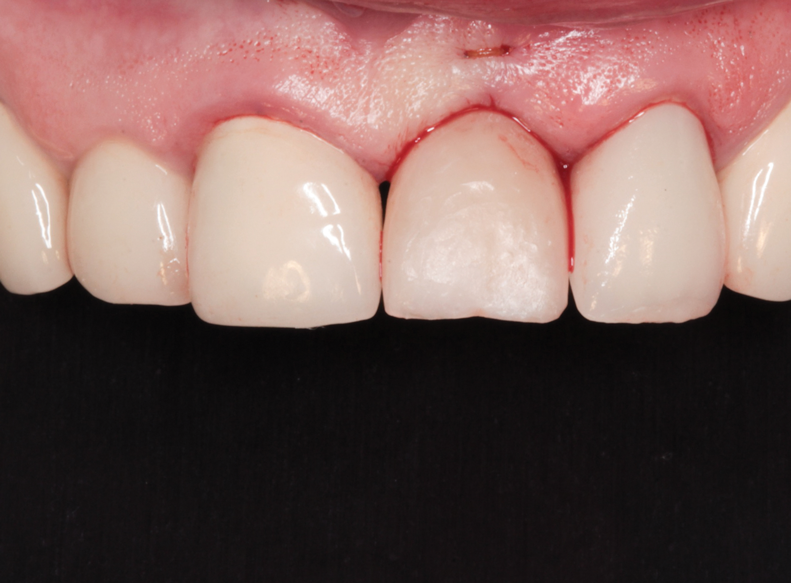

(56.) The provisional restoration was delivered and tightened to 15 Ncm while applying counter torque. Note that there is no pressure on the surrounding tissues and that the gingival embrasures were left open to allow for maximum incisal migration of the gingiva and papillae. The palatal and incisal surfaces were evaluated and modified to ensure that there was no contact throughout the excursive range.

Figure 56

(57.) The provisional restoration was delivered and tightened to 15 Ncm while applying counter torque. Note that there is no pressure on the surrounding tissues and that the gingival embrasures were left open to allow for maximum incisal migration of the gingiva and papillae. The palatal and incisal surfaces were evaluated and modified to ensure that there was no contact throughout the excursive range.

Figure 57